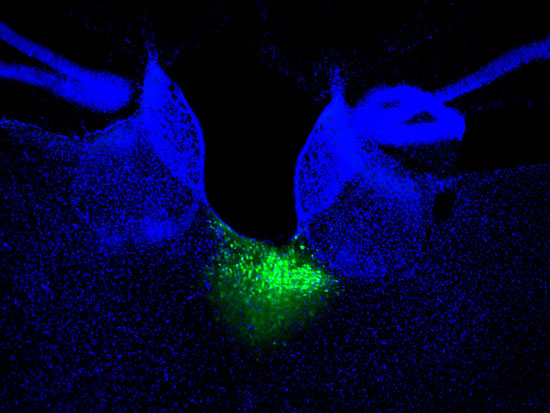

荧光标记的丘脑室旁核(pvt)(分离图) 论文作者供图

图片尺寸550x413